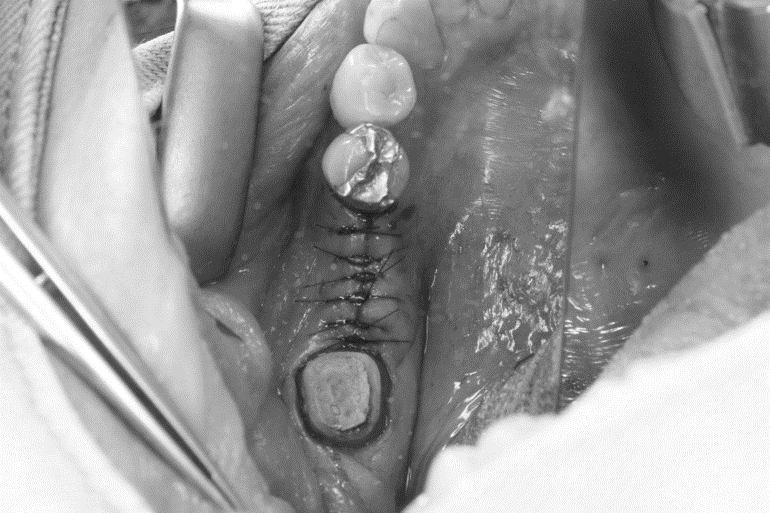

インプラントオペ

こんにちは。 南館歯科クリニックの木村です。 先日のインプラントオペの症例をご紹介します。 今回オペを行った部位は、前後の歯を土台にしたブリッジが入っていました。 その土台の歯が2次虫歯になり、なおか…